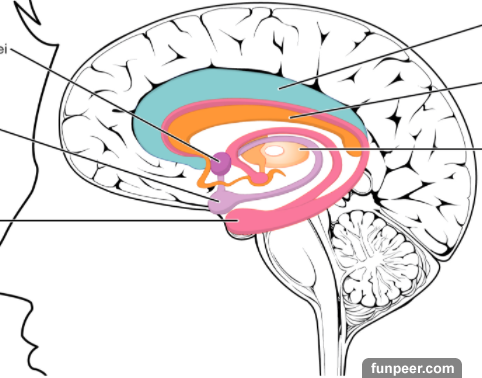

醫生檢查後發現,小李患上了腦動脈瘤。然而,這種病其實很常見,不管男女老少,有沒有家族病史,大家都可能罹患這種病,算是常見的腫瘤。小李的動脈瘤,讓她的血管像氣球一樣膨脹,壓迫到動脈瘤周圍的腦組織,讓她頭痛!

可是小李卻永遠無法回來了,再也無法抱抱8歲的小兒子!醫生說「腦動脈瘤」造成的血管擴張,其實不一定致命!如果動脈瘤急劇膨脹,甚至爆裂的時候,病人的生命就危險了!